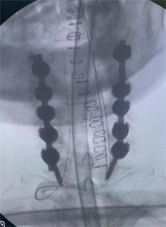

8. 机器人导航辅助下脊柱侧弯矫正技术

脊柱侧弯是一种复杂的脊柱三维畸形,其中以青少年特发性脊柱侧凸最常见。好看视频下载

在浦口地区率先开展机器人导航辅助下脊柱侧弯矫正术,实现了脊柱侧弯手术准确、微创、智能化的突破,获得了良好的效果。还有老年人退变性侧弯,机器人亦可精准置入困难椎弓根螺钉,误差只有0.3mm。